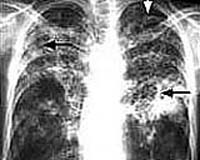

X-ray of tuberculosis infected lungs.